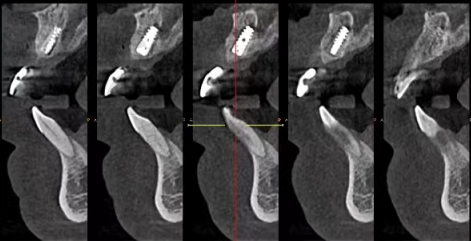

深圳穗华口腔医院在应急处理方面具有专精的实力。医院拥有精良的设备和技术,能够为患者提供精细的诊断和有效的治疗。例如,在数字化种植技术方面,采用德国ICX导航种植系统,术前3D模拟误差≤0.1mm,能有效避免损伤神经血管。即使是在急诊情况下,对于需要种植牙齿的患者,也能提供安心、精细的手术。